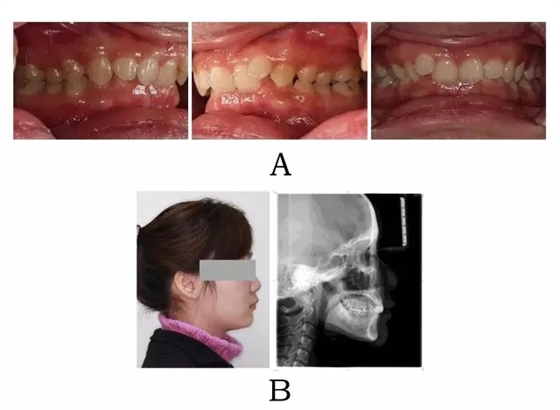

面型前突,面下部高度不足,頦唇溝較深??趦?nèi)表現(xiàn)為上頜骨源性前突,上前牙代償性直立或輕度唇傾;下頜后退伴深覆合深覆蓋,磨牙系遠(yuǎn)中關(guān)系。頭顱側(cè)位片下頜骨體部呈“長方形”,頦部形態(tài)較好(圖4-1)。

640.webp (1).jpg

圖4-1:混合I型突面畸形臨床表現(xiàn)及頭顱側(cè)位影像特征。

(A)齒槽與牙列特點(diǎn) (B)側(cè)貌與影像對比

Figure 4-1. Clinical manifestation and cephalometric image for merged skeletal and mandibular positional prognathism (Type I). (A) Alveolar and dentition specifics. (B) Facial profile and radiographic image.